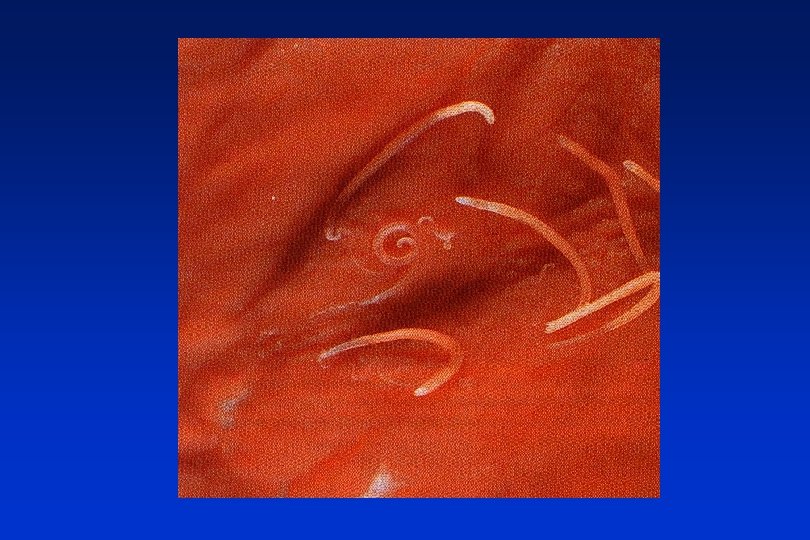

Ascariosis Ascaris lumbricoides

Roundworms (Nematodes) • Ascaris lumbricoides • Enterobius, Oxyuris vermicularis • Trichuris trichiura

Helmintic GI infections • Roundworms (Nematodes) - ascariosis, enterobiosis=oxyuriosis, trichuriosis • Tapeworms (Cestodes) - teniosis, diphylobotriosis, hymenolepsiosis, echinococcosis, alveococcosis • Flukes (Trematodes) - schistosomosis